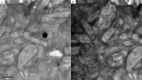

Transmission electron micrographs of LVC-loaded CCPCs. Abbreviation: LVC: levocetirizine hydrochloride and CCPCs; cationic ceramide/phospholipid composite.